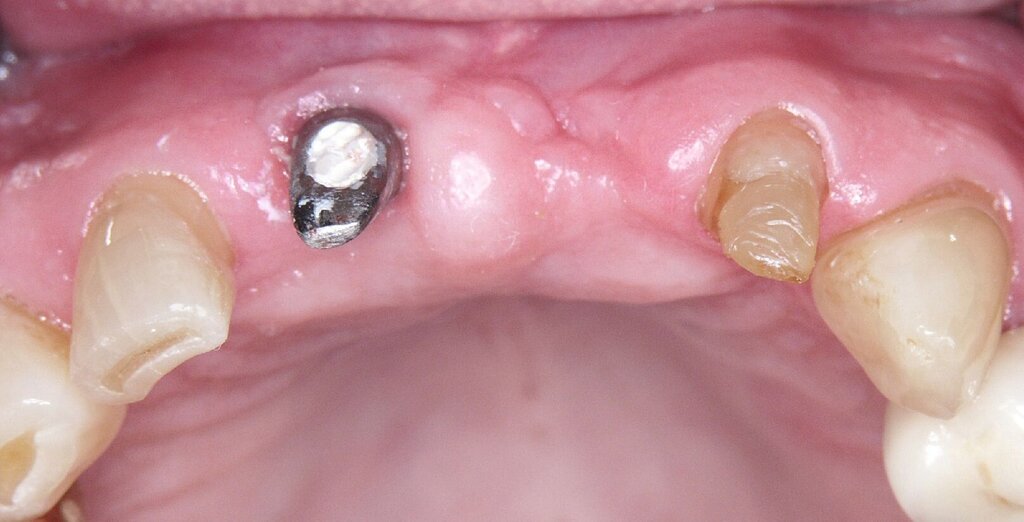

Ursprünglich waren bei dieser Patientin nach einem Frontzahntrauma vier Implantat-gestützte Kronen geplant. Nach dem frühen Verlust des Implantats in regio 21 während der Einheilzeit wurde dann eine auf drei Implantaten abgestützte Brücke eingegliedert. Das bestehende vertikale und horizontale Weichgewebsdefizit wurde bei der verschraubten Implantatbrücke durch aufgebrannte rosafarbene Keramik kaschiert (Abb. 3a). Funktionell war die Brückenversorgung über viele Jahre erfolgreich und zeigte keinerlei Lockerungsgrad. Trotz guter Mundhygiene war in Kontrollsitzungen ein kontinuierlicher Knochenabbau an allen Implantaten festzustellen (Abb. 3b). Zur Vermeidung eines weiteren Knochenverlusts fiel circa 15 Jahre nach der Erstversorgung die Entscheidung zur Explantation. Zu diesem Zeitpunkt war die Patientin 55 Jahre alt.

Nach dem Abschrauben der Suprastruktur (Abb. 3c und 3d) wurden alle Implantate unter Lokalanästhesie mit einem passenden Trepanbohrer umbohrt und ohne Lappenbildung entfernt. Die temporäre Lückenversorgung erfolgte mit einer herausnehmbaren Prothese, die über Gussklammern am Restgebiss abgestützt war.